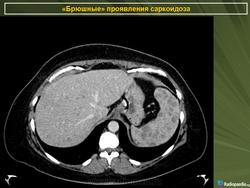

Саркоидоз селезенки и печени

Хотя саркоидоз печени и/или селезёнки обычно протекает бессимптомно, а увеличение уровня ферментов печени может быть небольшим, по данным исследователей из Японии методы визуализации (УЗИ брюшной полости, РКТ, ЯМР-томография и сканирование с галлием и технецием) могут легко выявить патологию. При лапароскопии можно видеть множественные узелки по поверхности печени или селезёнки, биопсия которых выявляет неказеифицированные эпителиоидные гранулёмы, содержащие многоядерные гигантские клетки, что особенно часто обнаруживают в области ворот органа (Kitamura M., Ishizaki T., 1994).

По мнению греческих рентгенологов очаговые изменения в селезёнке и печени являются необычными проявлениями абдоминального саркоидоза. Они описали случай саркоидоза, когда имелись множественные очаговые изменения пониженной плотности в печени и селезёнки на РКТ органов брюшной полости при нормальной рентгенограмме органов грудной клетки. Диагноз был подтверждён биопсией печени (Thanos L. et al., 2002).